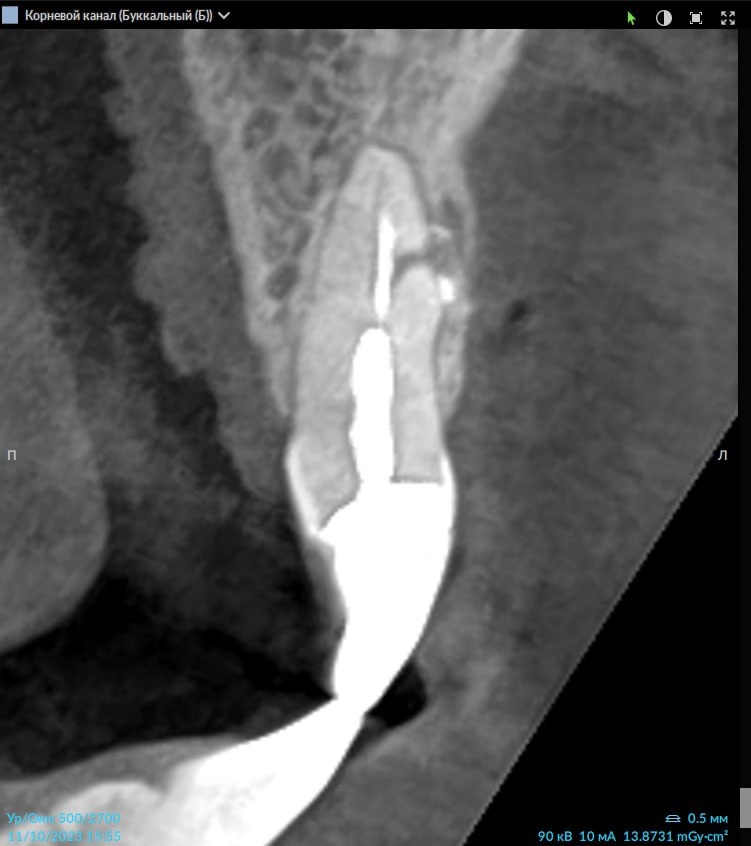

От хода основного канала отходит дополнительный канал под 90° - латеральное ответвление:

Рис. 1

Может выходить на вестибулярную (1 и 3 рис.) или палатинальную поверхность корня, что создает сложность обнаружения при помощи классической 2D-рентгенографии:

Рис. 3

В данном кейсе, работая в DTX Studio Clinic, использовали вкладку ENDO, которая позволяет вращать плоскость реформата вокруг оси канала зуба